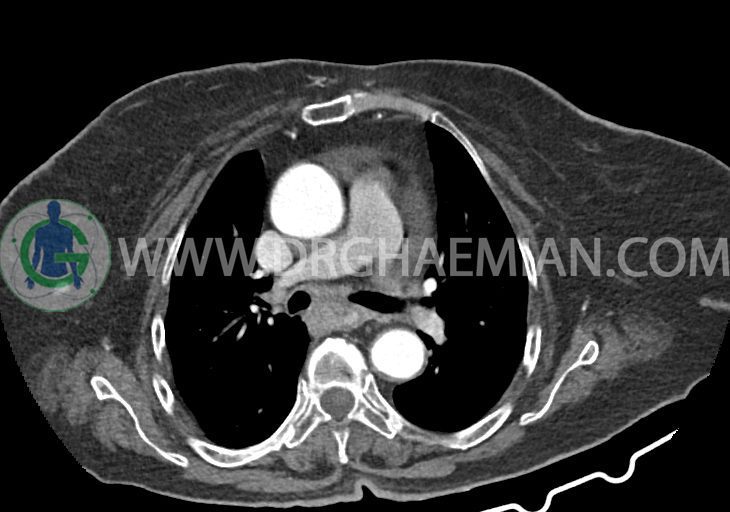

در سی تی اسکن اسپیرال ریه و مدیاستن – شکم و لگن با و بدون کنتراست خوراکی و وریدی (مولتی دیدکتور 16 با مقاطع ظریف و بازسازی های ساژیتال و کرونال):

–دیلاتاسیون نیمه فوقانی مری توراسیک ناشی از افزایش ضخامت circumferential توده مانند در یک سوم دیستال مری به طول 50mm ، که می تواند مطرح کننده انفیلتراسیون تومورال همراه با تنگی

–یک ندول به ابعاد 19x18mm با حدود اسپیلوکه در سگمان لترال RML و دو ندول کوچکتر در مجاورت فوقانی آن به اقطار 6mm و 5mm ( مطرح کننده کارسینوم برونکوژنیک یا متاستاز )